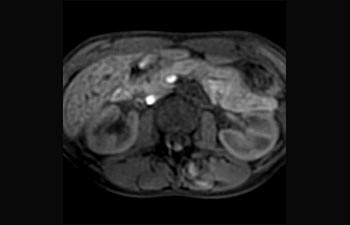

Hígado y páncreas